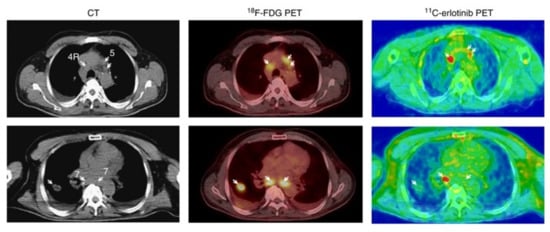

- Bahce, I.; Smit, E.F.; Lubberink, M.; Van Der Veldt, A.A.M.; Yaqub, M.; Windhorst, A.D.; Schuit, R.C.; Thunnissen, E.; Heideman, D.A.M.; Postmus, P.E.; et al. Development of [11C]erlotinib Positron Emission Tomography for In Vivo Evaluation of EGF Receptor Mutational Status. Clin. Cancer Res. 2013, 19, 183–193. [Google Scholar] [CrossRef]